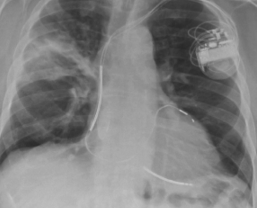

Andrew L. Chan, MD, MB, FCCP, FRCP; Jordan D. Fein, MD; Timothy E. Albertson, MD, PhD, FRCP

<p>THE CASE: An 81-year-old retired obstetrician who had never smoked tobacco presented with a 6-week history of cough with clear sputum, fever, chills, and a 30-lb weight loss. He...